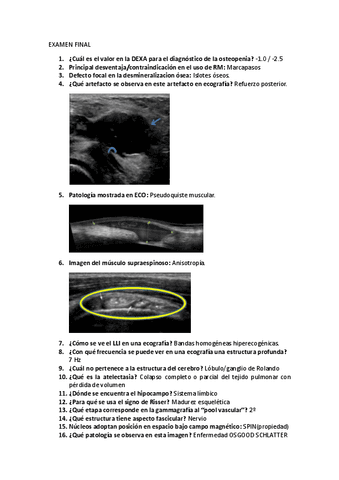

Exámenes - Examen-final-2023.pdf